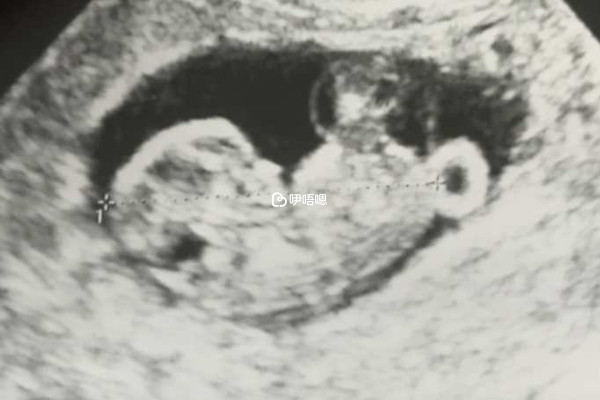

孕期的NT检查是通过超声检测胎儿颈部透明带厚度,根据检查结果排查胎儿先天性异常、染色体异常、心血管系统异常等,又称早期唐氏筛查,是一种常规产检,所以NT单子上的数据看男女是不准确的,不管是通过数值还是图像,网络上流传有一些NT单子看男女的经验总结,下面分享一些: